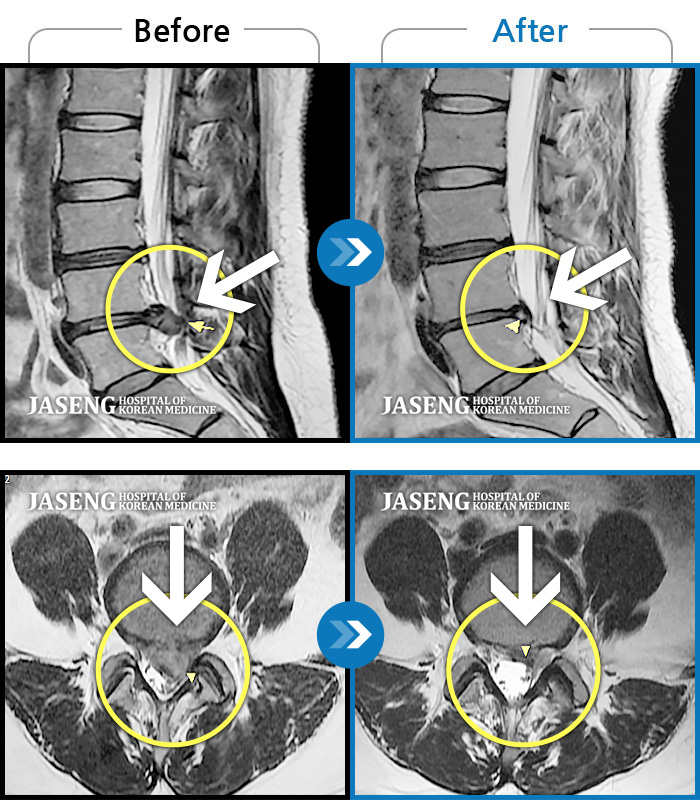

허리디스크

해운대 · 김상돈 원장

허리 골반 통증이 있고 허리를 숙일 때 불편합니다.

촬영시기

2020.09.14 ~ 2025.07.09

2025.07.11

조회수 325